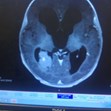

Лекарите казали, че това е бил сигнал за това, че в мозъка се натрупва течност. В същия ден на детето била направена компютърна томография на мозъка и тя установила масивен съсирек. Детето веднага било хоспитализирано в болница в Ливърпул. По думите на лекарите, туморът се е появил преди около седем месеца. И така изведнъж всичките подозрителни симптоми, появили се у сина на Джени, наредили пъзела на болестта.

Шест дни след поставянето на страшната диагноза момчето било подложено на операция, която отнела пет аса. Хирурзите успели да отстранят целия тумор. Биопсията показала, че той е бил раков – рак на хороидния плексус в трета фаза. Шансовете за оцеляване са се увеличили с 25%, след като момчето преминало и шестмесечен курс на химиотерапия.